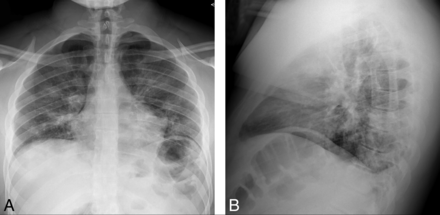

A 21-year-old man presented to the emergency department with progressive 4-day history of fever, cough, dyspnea, diarrhea, nausea, headache, and sinonasal congestion. Aside from a medical history of hypertension, prediabetes, and class I obesity, the patient was otherwise healthy and denied tobacco, alcohol, substance abuse, or recent travel. Vital signs were remarkable for a body temperature of 37.5°C, blood pressure of 116/57 mm Hg, pulse of 76 beats per minute, and oxygen saturation of 95% on room air. Physical examination documented nonlabored respirations and clear lungs. Neurologic examination was intact. Chest radiographs (Fig 1) demonstrated patchy bilateral air space opacities without lobar consolidation.

Initial chest radiographs in a patient with COVID-19 and subsequent bifacial weakness and paresthesia subtype Guillain-Barré syndrome. Posterior-anterior (A) and lateral (B) upright chest radiographs demonstrate low lung volumes with patchy bilateral air space opacities, but no lobar consolidation.

During the next 24 hours, the patient experienced increased dizziness with oxygen saturation falling into the mid-80s documented by pulse oximetry. He returned to the emergency department febrile (body temperature of 39.1°C), mildly tachycardic (102 beats per minute), tachypneic (28 breaths per minute), and hypoxic (89% on room air). Chest radiographs demonstrated increased bilateral air space opacities, and a complete blood count revealed lymphopenia (absolute lymphocyte count of 0.7 K/mm3). He was admitted for oxygen support and monitoring, and blood oxygenation was weaned from 2 L by nasal canula to room air. He was discharged home on hospital day 4, and his sent-out testing confirmed COVID-19 positivity the day after discharge.

At the initial emergency department visit, chest radiography (Fig 1) was performed, and nasopharyngeal swab specimens were sent for multiplex reverse transcription polymerase chain reaction via a NxTAG Respiratory Pathogen Panel (Luminex) to assess adenovirus, influenza A, influenza B, parainfluenza 1, parainfluenza 2, parainfluenza 3, parainfluenza 4, Chlamydia pneumoniae, Mycoplasma pneumoniae, bocavirus, coronavirus, respiratory syncytial virus A, respiratory syncytial virus B, metapneumovirus, rhinovirus, and enterovirus infection (On-line Table 5). Additional nasopharyngeal and oropharyngeal swab specimens were sent to an outside private laboratory (Viracor Eurofins Clinical Diagnostics) for SARS-CoV-2 real-time reverse-transcriptase polymerase chain reaction testing. During subsequent hospital readmissions and before final discharge, COVID-19 status was tested with nasopharyngeal/oropharyngeal swabs and SARS-CoV-2 PCR assays performed at our hospital laboratory.